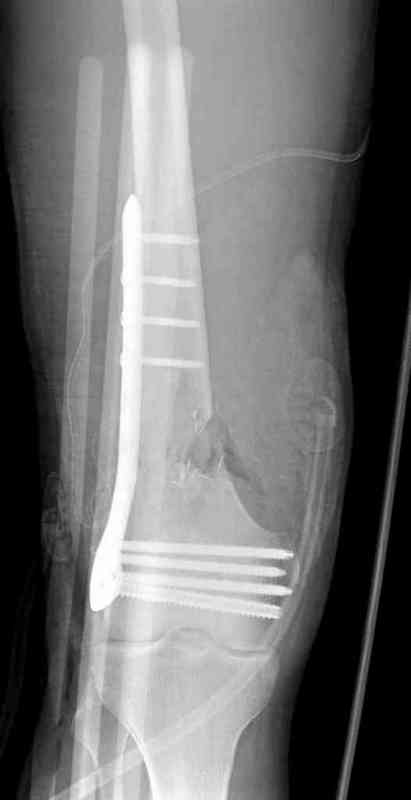

Re: The patient with non-union of the distal femur

Вчера утром поступил больной с огнестрельной раной, осмотрен сосудистым специалистом, сделана ангиограмма (снимки) Во время операции при вскрытии обнаружили кровотечение, рану забили салфетками, установили пластину locking DePuy.

Из-за возрастающего давления в компартменте сделана фасциотомия и вызванный сосудистый хирург ушил разрыв вены на уровне перелома. Все раны оставлены открытими, в пятницу закроем.